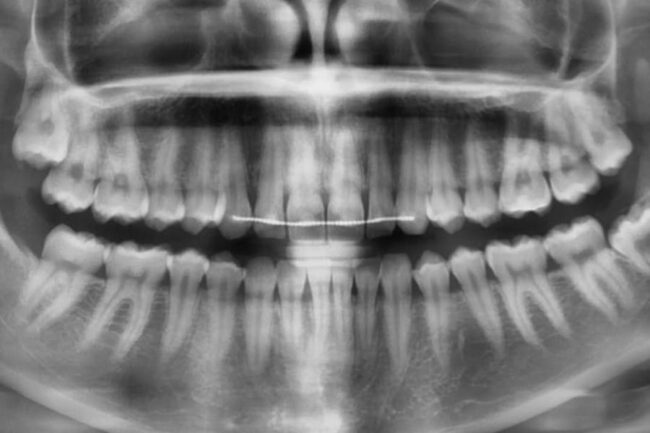

Panorámaröntgen a pontos diagnózishoz lehet fontos, amihez átfogó képet kell kapjunk az állkapcsokról, a fogakról és a környező szájüregi struktúrákról. A panoráma-röntgenfelvételek ebben segíthetnek.